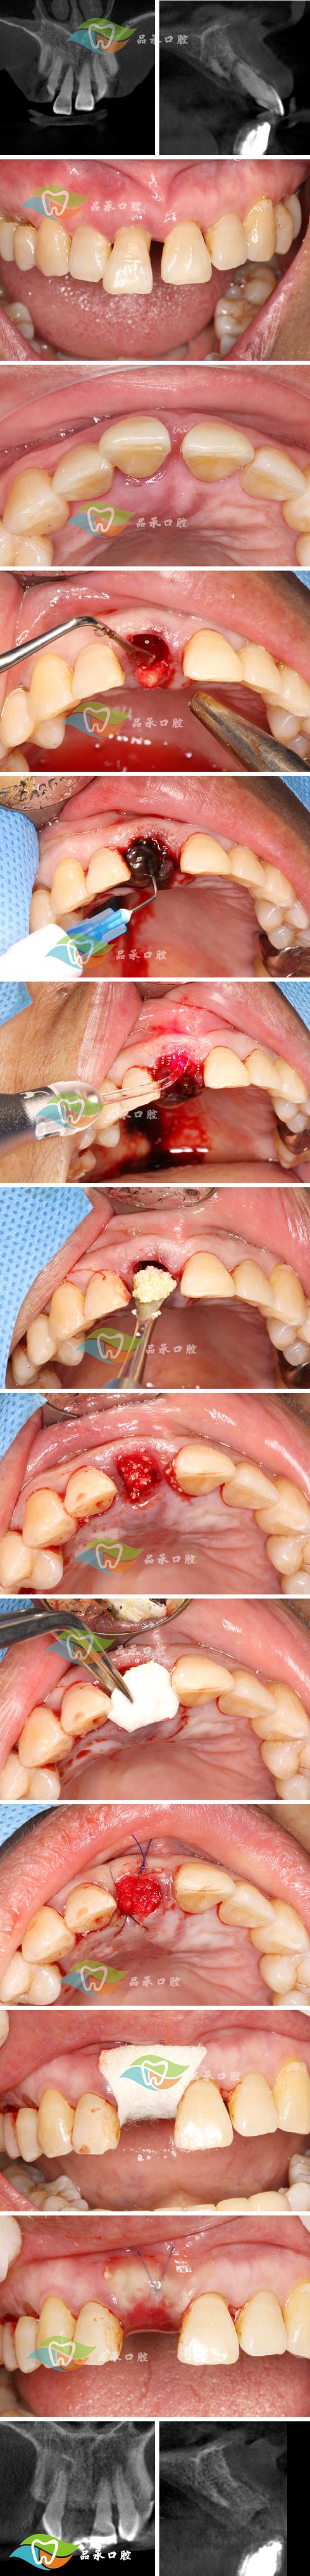

牙槽植骨是口腔种植修复中常见的手术,主要用于解决因牙齿缺失、牙周炎、外伤等原因导致的牙槽骨量不足问题,为种植体提供足够的骨支持,确保种植牙的长期稳定性和功能,而在牙槽植骨术后,部分患者可能会发现植骨区域出现黏膜发白的现象,这一表现既可能是正常的愈合过程,也可能提示异常情况,需结合具体症状和时间综合判断。

牙槽骨是上下颌骨包围和支持牙根的部分,牙齿缺失后,由于缺乏咀嚼刺激,牙槽骨会逐渐发生废用性萎缩,导致骨量不足(如宽度、高度不够),若直接在骨量不足的区域种植种植体,可能出现种植体暴露、松动、周围炎等问题,影响种植牙寿命,牙槽植骨即通过手术将自体骨、异体骨、异种骨或人工骨材料植入缺损区域,引导骨组织再生,恢复牙槽骨的形态和功能。

植骨材料的选择多样:自体骨(如髂骨、颏部骨)成骨活性高、无排异,但需额外取骨,增加创伤;异体骨(同种异体骨)经过处理,免疫原性低,但存在吸收风险;异种骨(如牛骨)来源广泛,生物相容性好,可能引起轻微免疫反应;人工骨(如羟基磷灰石、β-磷酸三钙)可降解,支撑作用稳定,但成骨速度较慢,不同材料的特性和术后反应存在差异,也可能影响黏膜颜色的变化。